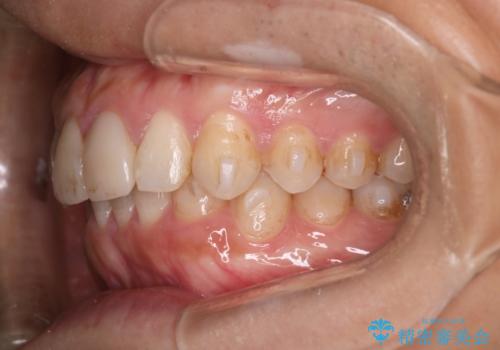

- 前歯のがたつきと口元を下げたいとのことで来院されました。

骨格的に左右差があるので正中を合わせることと抜歯矯正での口元改善は難しいことを説明させていただきました。

患者様に理解していただいた上で、インビザラインにてIPR(歯と歯の間を削る処置)を行いながら前歯のがたつきを整える治療計画を立てました。

インビザラインにて治療を行うことで、前歯のがたつきが改善されました。

左上1番目の前歯はセラミックをご希望されたので、セラミックにて被せ物の治療を行いました。

とても綺麗な前歯になりました。